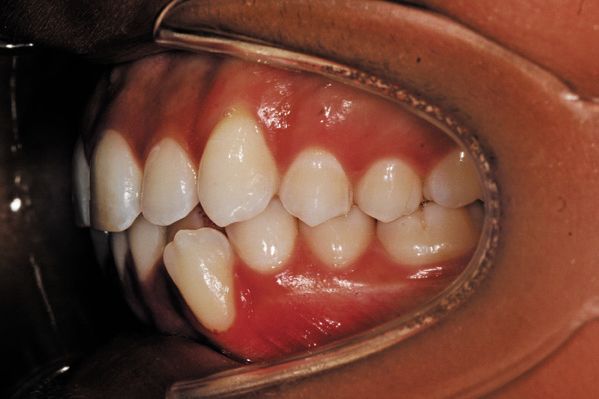

(6) Buccal left

Fig. 5: Left buccal photos for Invisalign records.